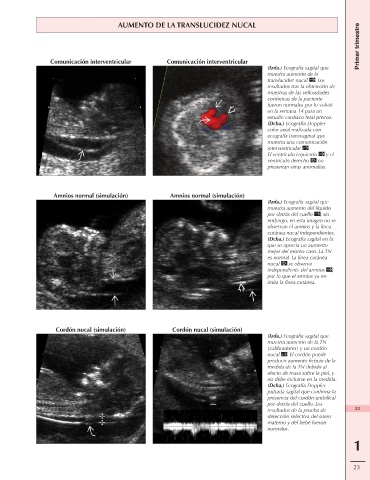

AUMENTO DE LA TRANSLUCIDEZ NUCAL

Comunicación interventricular Comunicación interventricular

(Izda.) Ecografía sagital que

muestra aumento de la

translucidez nucal . Los

resultados tras la obtención de

muestras de las vellosidades

coriónicas de la paciente

fueron normales por lo volvió

en la semana 14 para un

estudio cardíaco fetal precoz.

(Dcha.) Ecografía Doppler

color axial realizada con

ecografía transvaginal que

muestra una comunicación

interventricular .

El ventrículo izquierdo y el

ventrículo derecho no

presentan otras anomalías.

Amnios normal (simulación) Amnios normal (simulación)

muestra aumento del líquido

por detrás del cuello ; sin

embargo, en esta imagen no se

observan el amnios y la línea

cutánea nucal independientes.

(Dcha.) Ecografía sagital en la

que se aprecia un aumento

mejor del mismo caso. La TN

es normal. La línea cutánea

nucal se observa

independiente del amnios ,

por lo que el amnios ya no

imita la línea cutánea.

Cordón nucal (simulación) Cordón nucal (simulación)

muestra aumento de la TN

(calibradores) y un cordón

nucal . El cordón puede

producir aumento ficticio de la

medida de la TN debido al

efecto de masa sobre la piel, y

no debe incluirse en la medida.

pulsada sagital que confirma la

presencia del cordón umbilical

por detrás del cuello. Los

resultados de la prueba de 23

detección selectiva del suero

materno y del bebé fueron

normales.